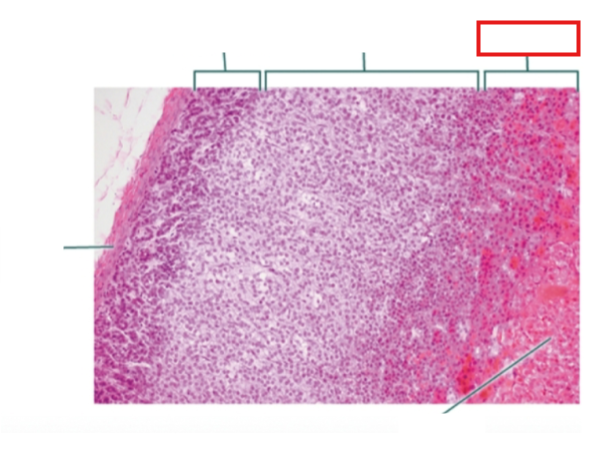

What structure is highlighted?

zona glomerulosa

What structure is highlighted?

zona fasciculata

What structure is highlighted?

zona reticularis

What structure is highlighted?

Capsule

What structure is highlighted?

medulla

What structure is highlighted?

capsule

What structure is highlighted?

zona glomerulosa

What structure is highlighted?

zona fasciculata

What structure is highlighted?

zona reticularis

What structure is highlighted?

adrenal medulla

What tissue is shown?

adrenal gland